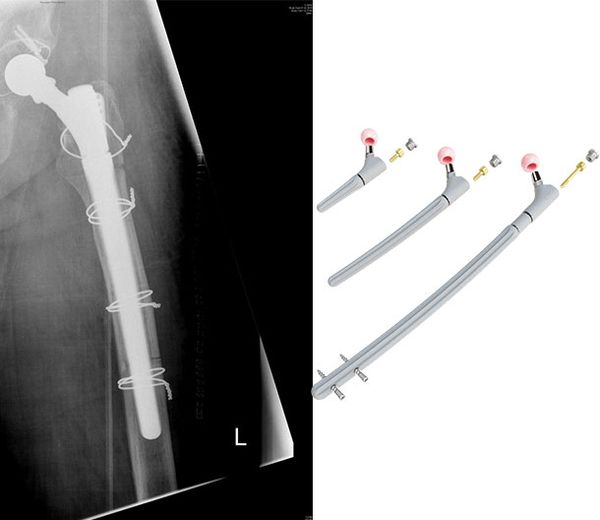

Bei Prothesenwechseln oder Knochenbrüchen um einliegende Hüftprothesen kommen wiederum Revisionsprothesen zum Einsatz, die sich weiter distal im Oberschenkelschaft verankern. Hierbei handelt es sich aber nie um primär implantierte Prothesen.